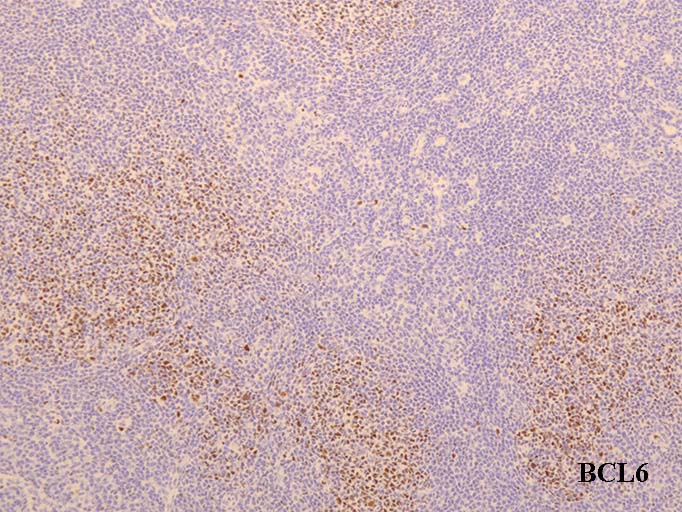

MIB-1(Ki67)-indexが低い濾胞は異常. CD10陽性細胞が濾胞辺縁や濾胞間にも見られるのは異常である---FL診断の重要な「必ずあってほしい~あってほしい所見」

MIB-1 labeling index(LI); 胚中心はlow. 濾胞外にCD10+細胞がこぼれている. 核型はt(14;18)の単独異常. 付加的異常はみられない.